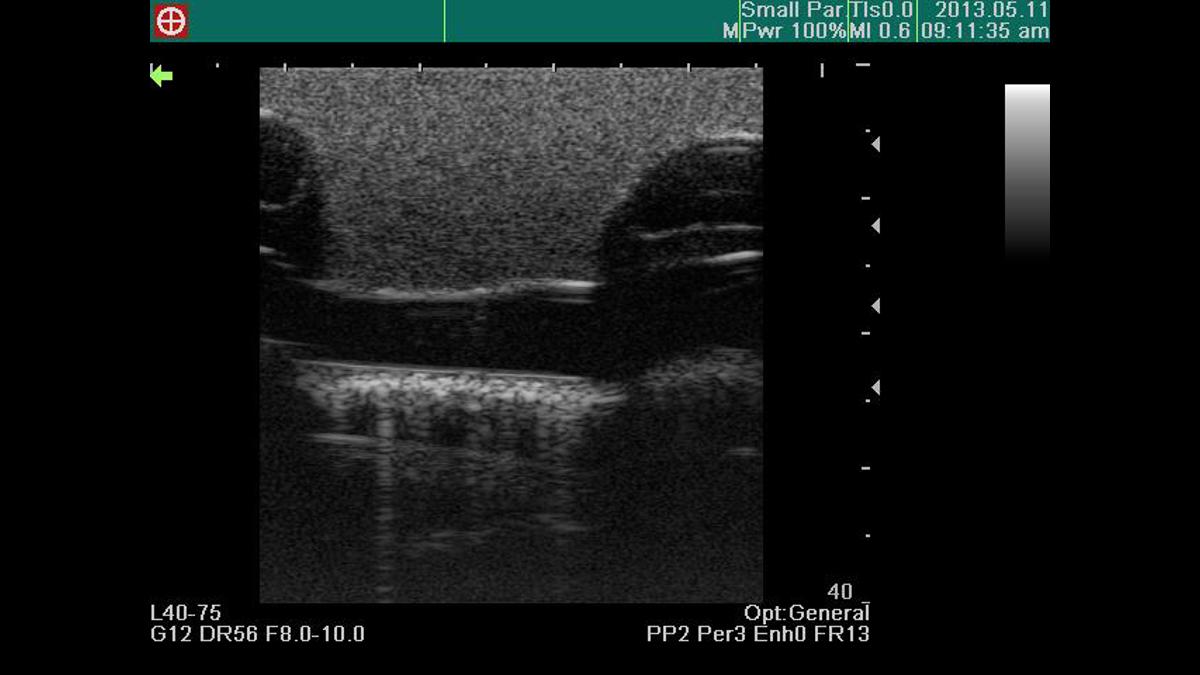

This ultrasound compatible model is a multifaceted trainer that facilitates training in thoracentesis and pericardiocentesis. The combined model allows trainees to use the clear ultrasound image provided to accurately perform both procedures.

Excellent ultrasound image

Anatomically correct puncture sites reproduce realistic needle-top resistance and sensation

Confirmation of ventricles, ribs, pericardium, liver and main artery under ultrasound scanning

Recognition of anatomical landmarks using ultrasound